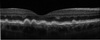

Quais são os achados típicos das drusas no OCT?

Elevações da Linha do EPR, separando-a de outra linha hiperrefletiva: a Membrana de Bruch